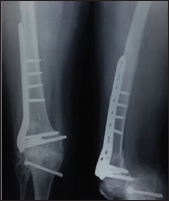

Figure 6: Followup Anteroposterior(AP) and lateral X–Ray of thigh at 24 weeks.

30 cases of supracondylar femur fracture were treated by open reduction and internal fixation (ORIF) with LCP between 1st October 2014 to 30th September 2016 at our tertiary level trauma centre. The patients were evaluated clinically and radiologically for outcomes using various parameters. The fracture was classified according to the AO classification system preoperatively on the Anteroposterior and lateral X-Rays (Figure 1). All the patients in this study were treated by open reduction and internal fixation by using standard lateral approach within four days of injury (Figure 2). The fracture was adequately exposed and reduced under C-arm guidance. K-wires were used to provisionally fix the fracture (Figures 3 & 4). LCP of appropriate length was used in each case according to the type of fracture (Figure 5). All patients were followed up for an average of 6 months. Check X-Ray was done at regular intervals to see the progress of the fracture union (Figures 6-8). The outcome was assessed using Neer's Score [23-26]. The fracture was considered united clinically when there was no pain on palpation, no discomfort on full weight bearing. Radiologically fracture was considered united when serial roentgenograms demonstrated bone trabaculae is crossing the fracture site. The functional outcome was evaluated by Neer's knee score criteria.